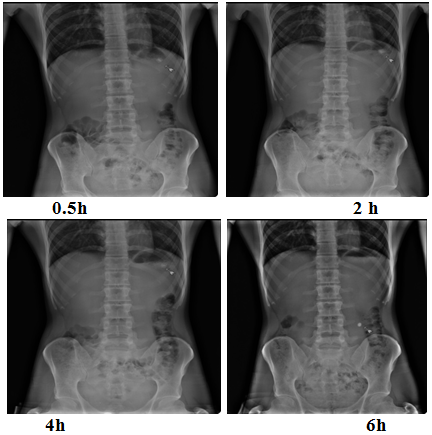

For this study, the tablets are prepared by replacing half the amount of drug with barium sulfate. After overnight fasting, the volunteers were fed with a low-calorie food. After half an hour, a barium sulfate-labeled tablet was given to every subject with 200 ml of water. The volunteers were asked to take 200 ml water after every 1h. At different time intervals (0.5, 2, 4, and 6 h post administration of tablets), the volunteers were exposed to abdominal X-ray imaging in standing position. The distance between the source of X-rays and the subject was kept constant for all images. Thus, the observation of the floating tablet movements could be easily noticed. The mean gastric retention period was estimated.

The radiographic images were taken at different periods post administration of the barium sulfate-loaded tablet in three human volunteers (fig. 12). It is clear that the tablet appears more or less at the same position for the initial 4h. This could be related to its floating ability. Later on, the tablet was slightly moved downwards, yet remained within the stomach till the end of 6 h. The increased gastric residence time favours an increase in the bioavailability of drugs.

Fig. 12: Radiographic images of optimized risperidone floating tablet (F15) in the stomach at different time intervals

An attempt was made to formulate and evaluate floating drug delivery system containing Risperidone as a model drug, from the data, obtained; it can be concluded that hydrodynamically balanced tablet of an antipsychotic drug Risperidone can be formulated as an approach to increase gastric residence time and thereby improve its bioavailability. Formulation F15 prolonged the release (99.45% up to 12 h) of the drug as compared to other prepared formulations. In vivo radiographic and bioavailability studies performed in healthy human volunteers. From radiographic studies, it is clear that the tablet remained within the stomach till the end of 6 h. Tmax, Cmax, AUC were calculated and confirmed significant improvement in bioavailability when compared with marketed formulation Respidon 2. The data obtained thus suggests that floating delivery system can be successfully designed to give controlled drug delivery, improved oral bioavailability and many other desirable characteristics.